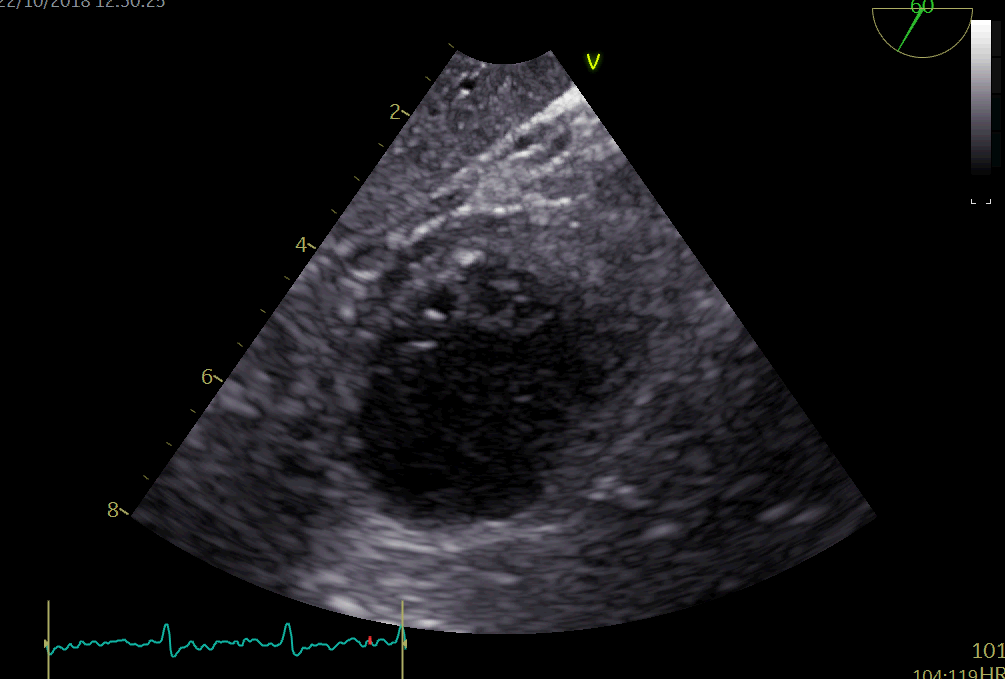

我需要有人帮我做一个项目。我的意图是用OpenCV和python裁剪声纳的视频,以便进一步处理它们。我要寻找的特征是:

现在,我有点卡在轮廓查找和裁剪部分。我想让OpenCV自动识别环绕超声形状的包围盒,知道所有的视频都有特定的圆锥形状。此外,如果能消除不相关的杂波,那就太好了。你能帮帮我吗?附加您可以找到一个原始帧的视频和希望的结果。